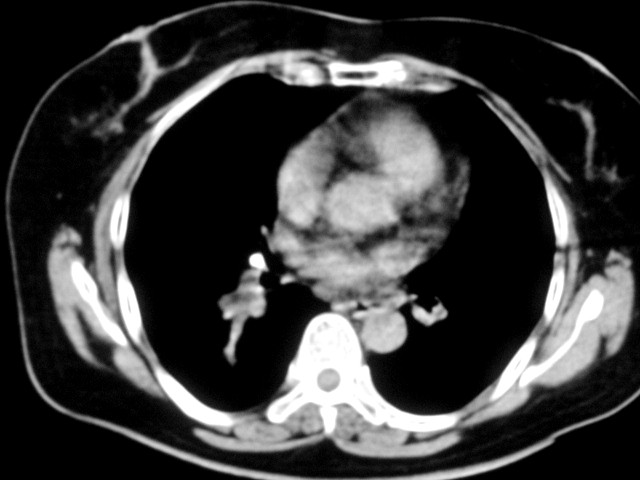

以下是引用清清楚楚在2007-8-28 7:13:00的发言:[br]右肺下叶可见斑片状高密度影,边缘模糊;右肺中叶内侧段及左肺舌段亦可见小斑片状模糊影。[br]考虑双肺感染,建议抗炎治疗后复查。

以下是引用天南地北在2007-8-27 23:49:00的发言:[br]右肺下叶可见斑片状高密度影,边缘模糊;右肺中叶内侧段及左肺舌段亦可见小斑片状模糊影。[br]考虑双肺感染,建议积极抗炎治疗后复查。

以下是引用难听在2007-8-28 13:17:00的发言:[br]右肺下叶背段支气管狭窄,是否可以考虑新生物伴阻塞性肺炎.请大家帮帮忙,这个病人是卫生局长的丈母娘.惹不起啊.